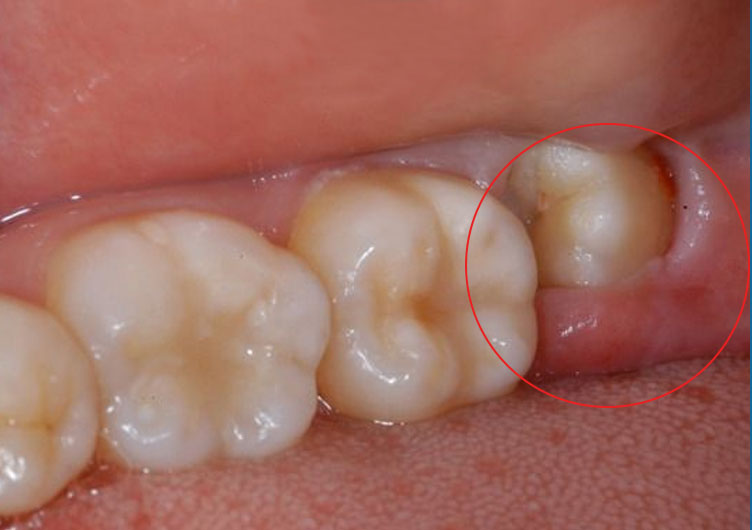

Lúc này, các răng khác đã phát triển hoàn chỉnh, chiếm hết chỗ nên răng số 8 thường không thể mọc bình thường mà sẽ có hiện tượng mọc lệch, mọc ngầm, mọc chen chúc. Điều này gây ra nhiều biến chứng khác nhau ở mỗi người, như:

- Do răng số 8 mọc lệch trong cùng cung hàm nên việc chăm sóc, vệ sinh răng miệng khá khó khăn khiến thức ăn có thể tích tụ lại.

- Khi không được vệ sinh kỹ sẽ tạo ra môi trường thuận lợi cho vi khuẩn xuất hiện, phát triển gây ra các bệnh lý nghiêm trọng như: bị sâu răng, viêm nha chu, viêm quanh chóp. Nếu để lâu ngày sẽ khiến răng bị lung lay hoặc nguy hiểm hơn là gây tiêu xương ổ răng.

- Răng số 8 mọc lệch, mọc chen chúc sẽ có xu hướng đâm vào bên cạnh chân răng số 7 khiến chiếc răng này dần dần bị hủy hoại, lung lay và dẫn đến gãy rụng, ảnh hưởng đến chức năng ăn nhai cũng như khó khăn trong quá trình sinh hoạt.